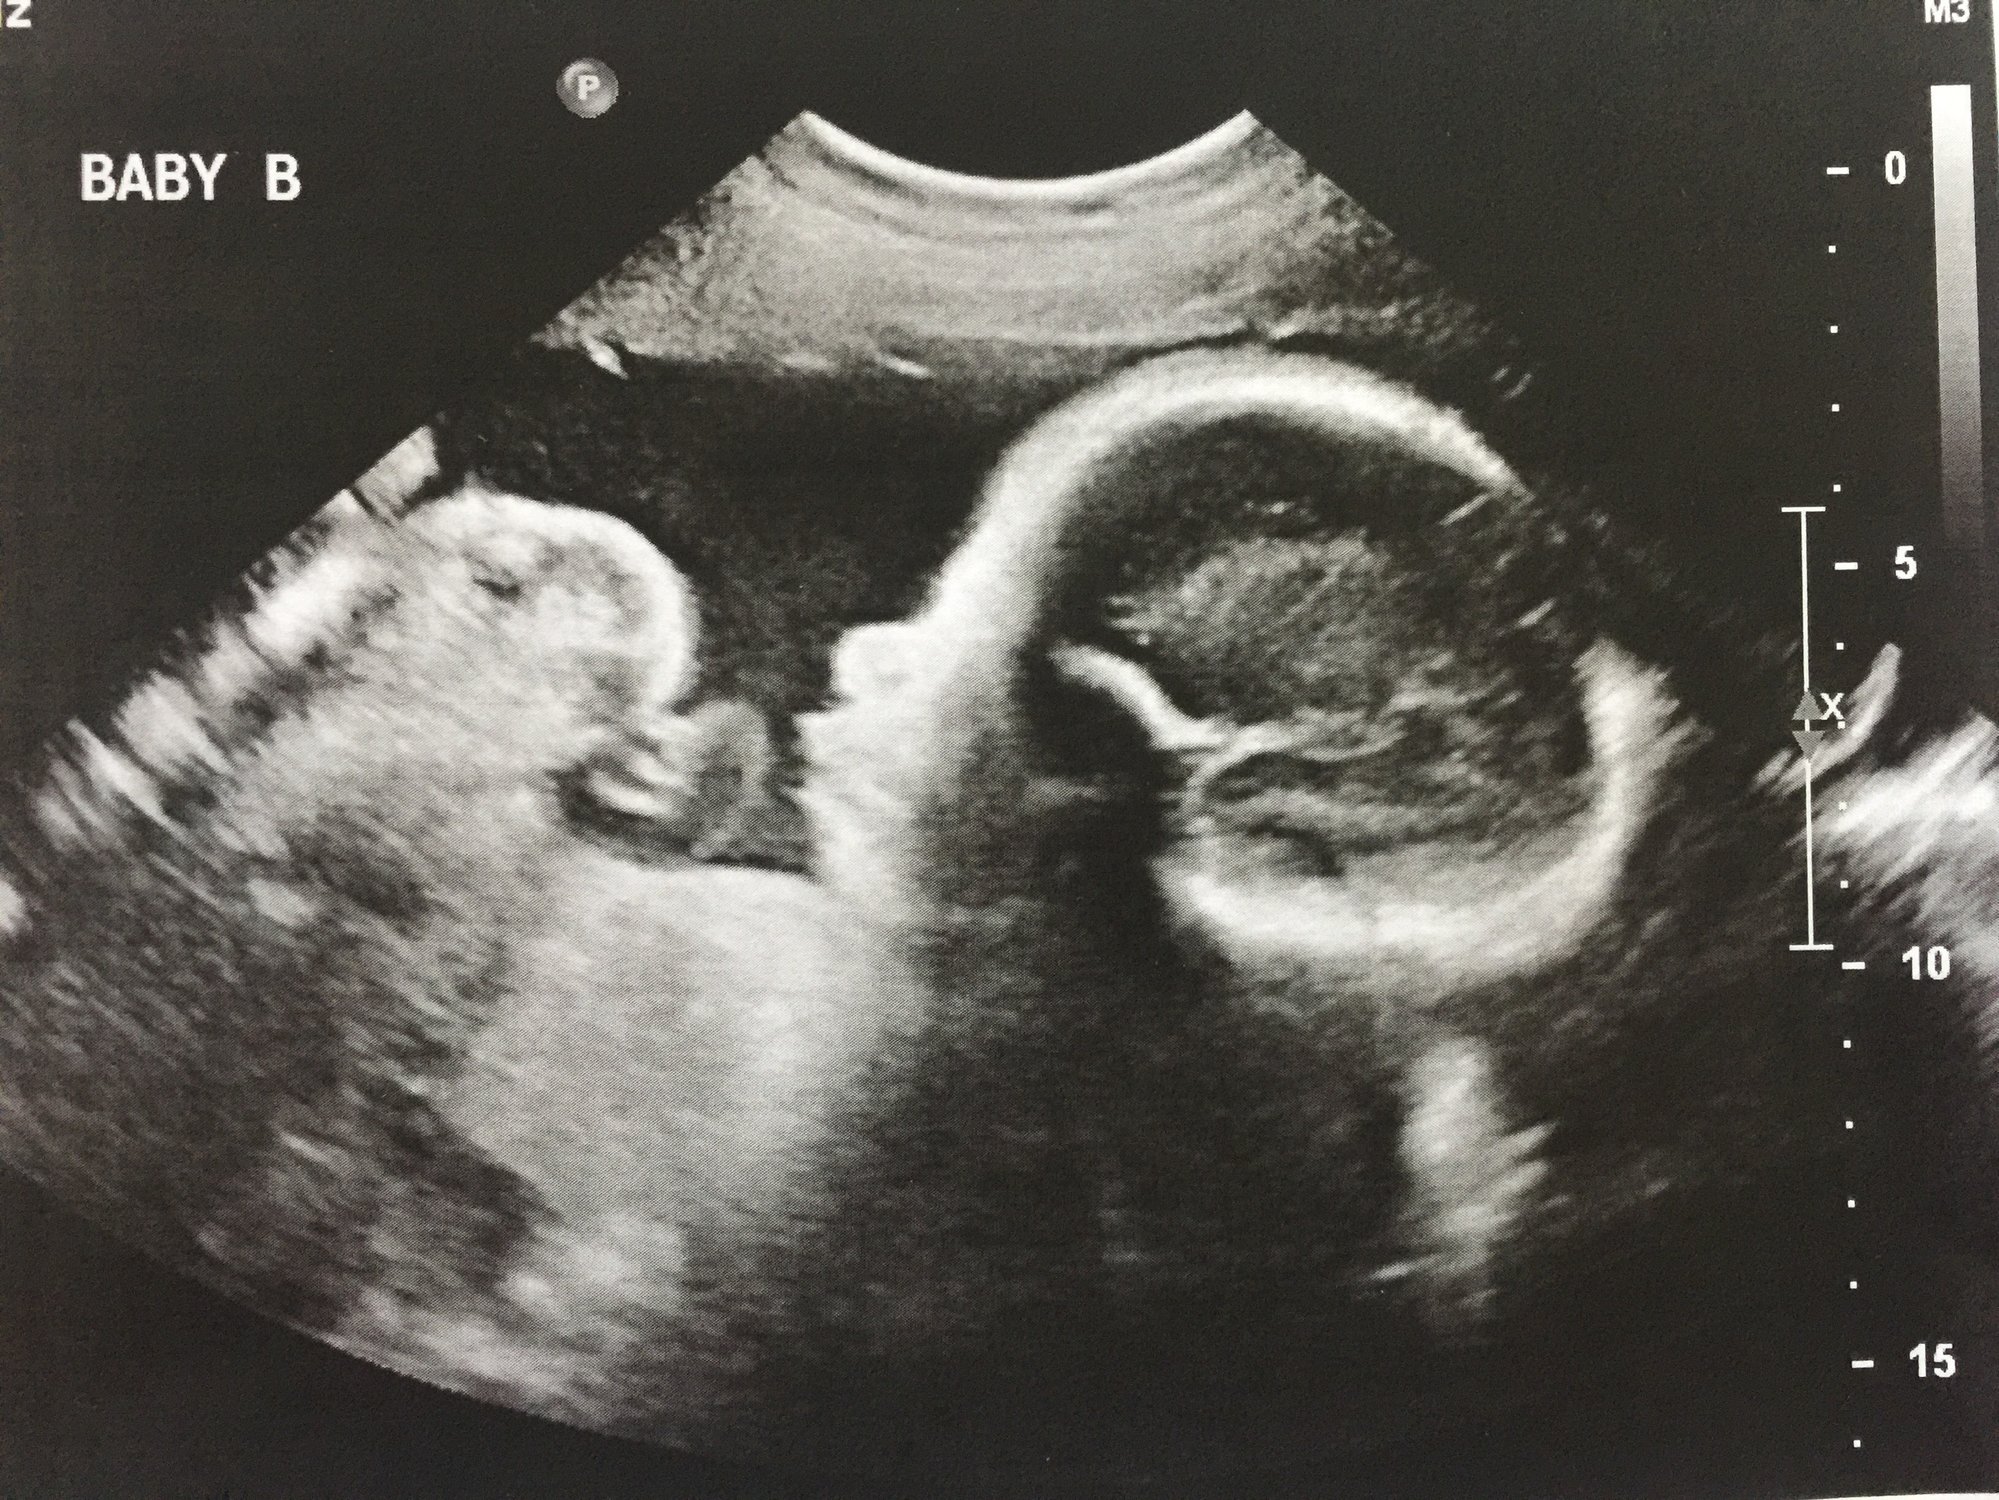

Ladies had my first NST today and it was great babies scored perfect on everything. I also got an ultrasound beforehand and finally got a pick of baby bs profile and a pick of the girls heads. Baby a weighs 3lbs 15 oz and baby b is 4lbs and 6oz crazy the size gap they have always been close in size here are the pics